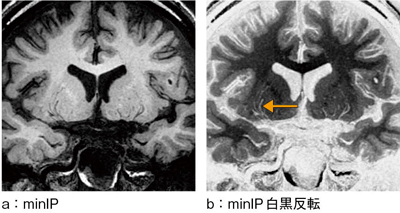

isoFSEを用いたT1強調画像は,数多くのecho factorを使用するため,流れている構造はflow voidとして表現される。動脈のような速い流れは低信号となるため,部分的な最小値投影法(minIP)によって動脈を連続的にすることが可能である。レンズ核線条体動脈などの穿通枝も,高い空間分解能によって描出することができる(図4)。図4 bは,動脈の構造が視覚的に認識しやすい白黒反転画像であり,←は穿通枝を示している。

図4 isoFSE T1強調画像